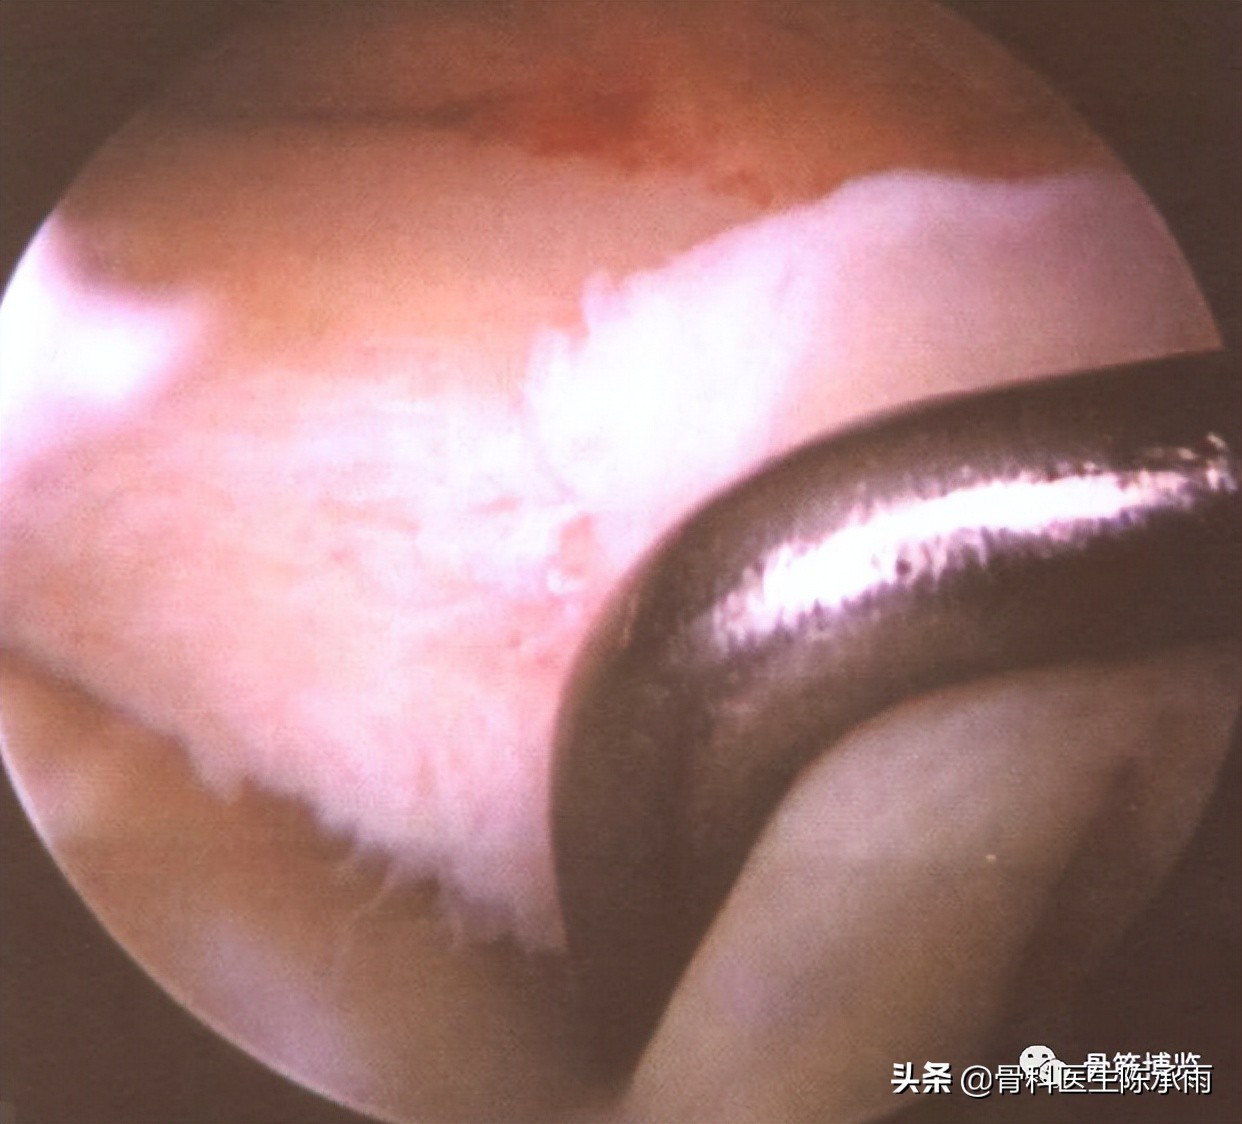

二、半月板损伤

内外侧均可发生。由于膝关节屈曲外翻伤较多,更易使外侧半月板受伤。我们的统计中外侧半月板损伤发生率为91.6%。半月板损伤由于挤压、碾转应力所致。根据损伤程度和类型,镜下所见有半月板边缘分离、提篮损伤并交锁、纵裂、层裂、横裂及复合损伤。关节镜检查发现半月板损伤,可根据其损伤类型及程度进行处理,由于滑膜连接部撕裂所致边缘游离者,缝合修补的效果很好;损伤严重难以保留者应予以全部切除;能够部分切除的应尽量保留;损伤较小(0.3~0.5mm)并位于外1/3区域时,可不予处理,术后经适当的固定多可愈合。

半月板损伤